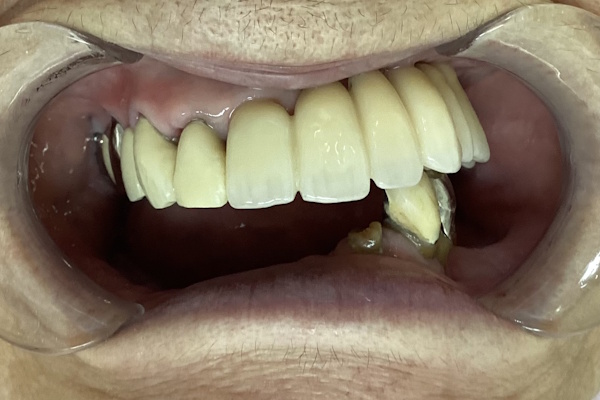

「噛み合わせられない/入れ歯が合わない」ということでご来院いただきました。インプラント治療で快適に噛めるようになりました。下顎はロケーターアタッチメント使用しています。

実際の見た目の写真